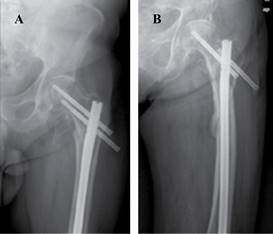

El tiempo medio de consolidación de la fractura en el grupo T2 Recon fue de 4.21 meses y de 4.09 meses para el grupo Gamma3 (Figura 1). En tres de los casos observamos un retardo de la consolidación, uno del grupo Gamma3 y dos en el grupo T2 Recon. En el caso del Gamma3 la consolidación final se dio a los seis meses tras realizar una nueva cirugía dinamizando el enclavado. Los dos casos del grupo T2 Recon presentaron un fallo por fatiga del material, se rompió el clavo en ambos casos. El primero de los casos fue un T2 Recon de 9 mm, la reducción de la fractura fue óptima, así como la posición del implante, el cual se rompió a los 4.5 meses de la cirugía. Se reintervino al paciente, se retiró el material roto y se implantó de nuevo un T2 Recon de 9 mm, dada la imposibilidad de poner un clavo de mayor diámetro por presentar un canal medular estrecho. Finalmente, la fractura consolidó a las 10 semanas (Figura 2). El segundo caso de rotura de material fue un T2 Recon de 11 mm de diámetro a los seis meses postoperatorios, se reintervino al paciente y se implantó un Gamma3 largo de 11 mm, consiguiendo la consolidación final de la fractura a las 12 semanas postoperatorias.

Figura 2: Caso clínico 2: rotura de clavo T2 Recon. Retirada de material e implante de nuevo T2 Recon. Consolidación final a las 10 semanas.